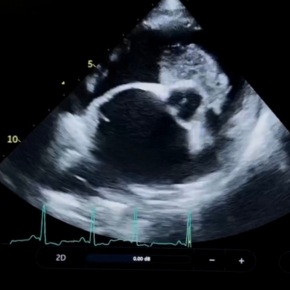

To assess how pimobendan monotherapy affected heart size over time (specifically left atrial and left ventricular dimensions) in dogs with myxomatous mitral valve disease.

Echocardiographic data from 31 dogs with myxomatous mitral valve disease presenting to two referral centres was retrospectively analysed. Dogs were divided into a control group (7 dogs not receiving pimobendan) and an intervention group (24 dogs receiving pimobendan in accordance with the 2019 ACVIM consensus criteria). All dogs had no evidence of congestive heart failure, had no concurrent congenital or acquired structural cardiac disease, had no systemic hypertension or significant systemic illness, and were not receiving any other cardiac medications (including diuretics, ACE inhibitors, spironolactone or amlodipine).

Dogs receiving pimobendan showed a reduction in normalised diastolic left ventricular internal dimension (LVIDdN) and a decrease in LA:Ao at follow-up, showing evidence of reverse remodelling in patients with Stage B2 MMVD treated with chronic pimobendan monotherapy.